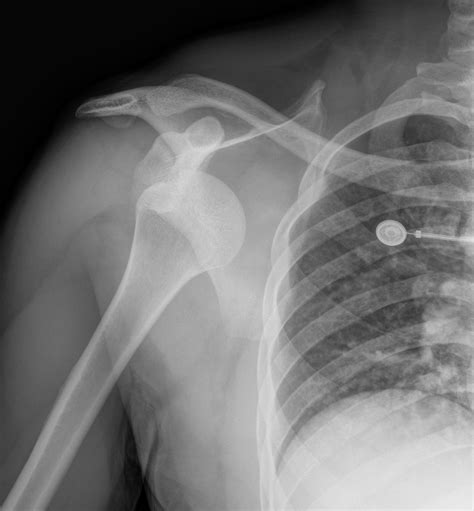

Diagnosis of Inferior Shoulder Dislocation

Diagnosing an inferior shoulder dislocation involves a combination of physical examination and imaging tests. The diagnostic process typically includes:

• Physical examination: A healthcare provider will assess the shoulder for deformity, swelling, and range of motion.

• X-rays: Imaging tests can confirm the dislocation and rule out fractures or other injuries.

• CT scan or MRI: These advanced imaging techniques may be used to evaluate the extent of the injury and plan treatment.

Accurate diagnosis is crucial for determining the appropriate course of treatment and ensuring a successful recovery.